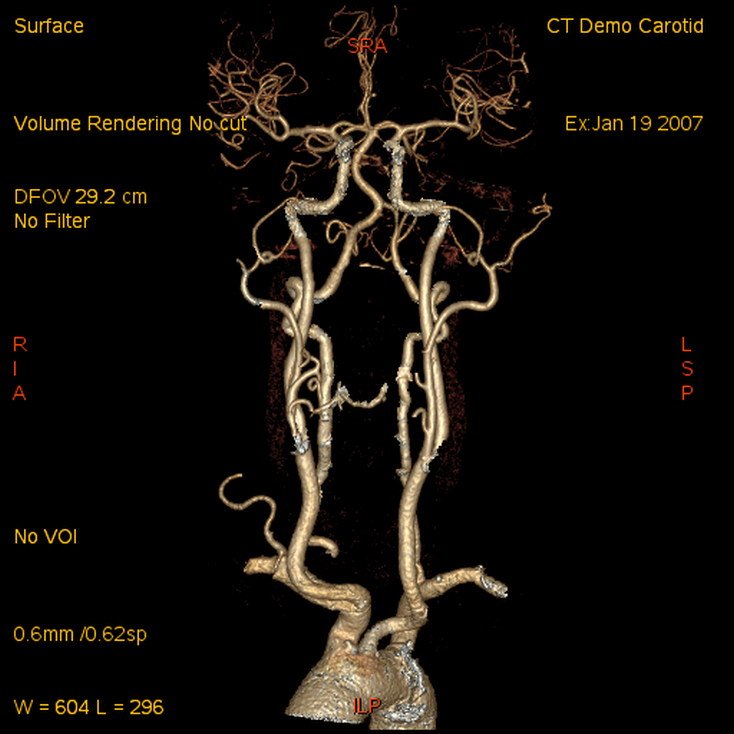

CT Angiography head & neck

Lower Limb Angiography